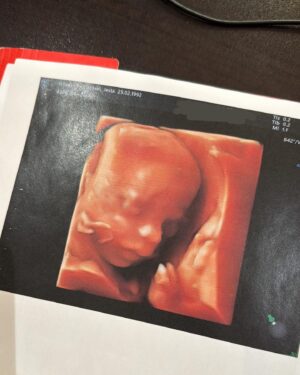

132.7K Likes – Jesta Hillmann Instagram

Caption : T2 morphologie et je dois vous annoncer QUE TOUT VA BIEN 🥹🤍 Il n’y a plus d’hématomes et bébé va super bien, il grandit parfaitement et se développe à merveille 🙏🏼Likes : 132683

132.7K Likes – Jesta Hillmann Instagram

Caption : T2 morphologie et je dois vous annoncer QUE TOUT VA BIEN 🥹🤍 Il n’y a plus d’hématomes et bébé va super bien, il grandit parfaitement et se développe à merveille 🙏🏼Likes : 132683